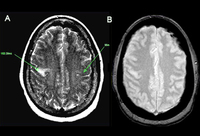

Acidente vascular cerebral (AVC) isquêmico

Dados dos ensaios clínicos DAWN e DEFUSE-3 (fluxo sanguíneo cerebral [FSC]; tempo até o máximo [Tmáx]; artéria carótida interna [ACI]; artéria cerebral média [ACM])

Criado no BMJ Knowledge Centre utilizando dados de Dawn-Nogueira et al. N Engl J Med. 2018 378(1):11-21 and Defuse-Albers et al. N Engl J Med. 2018 22;378(8):708-18